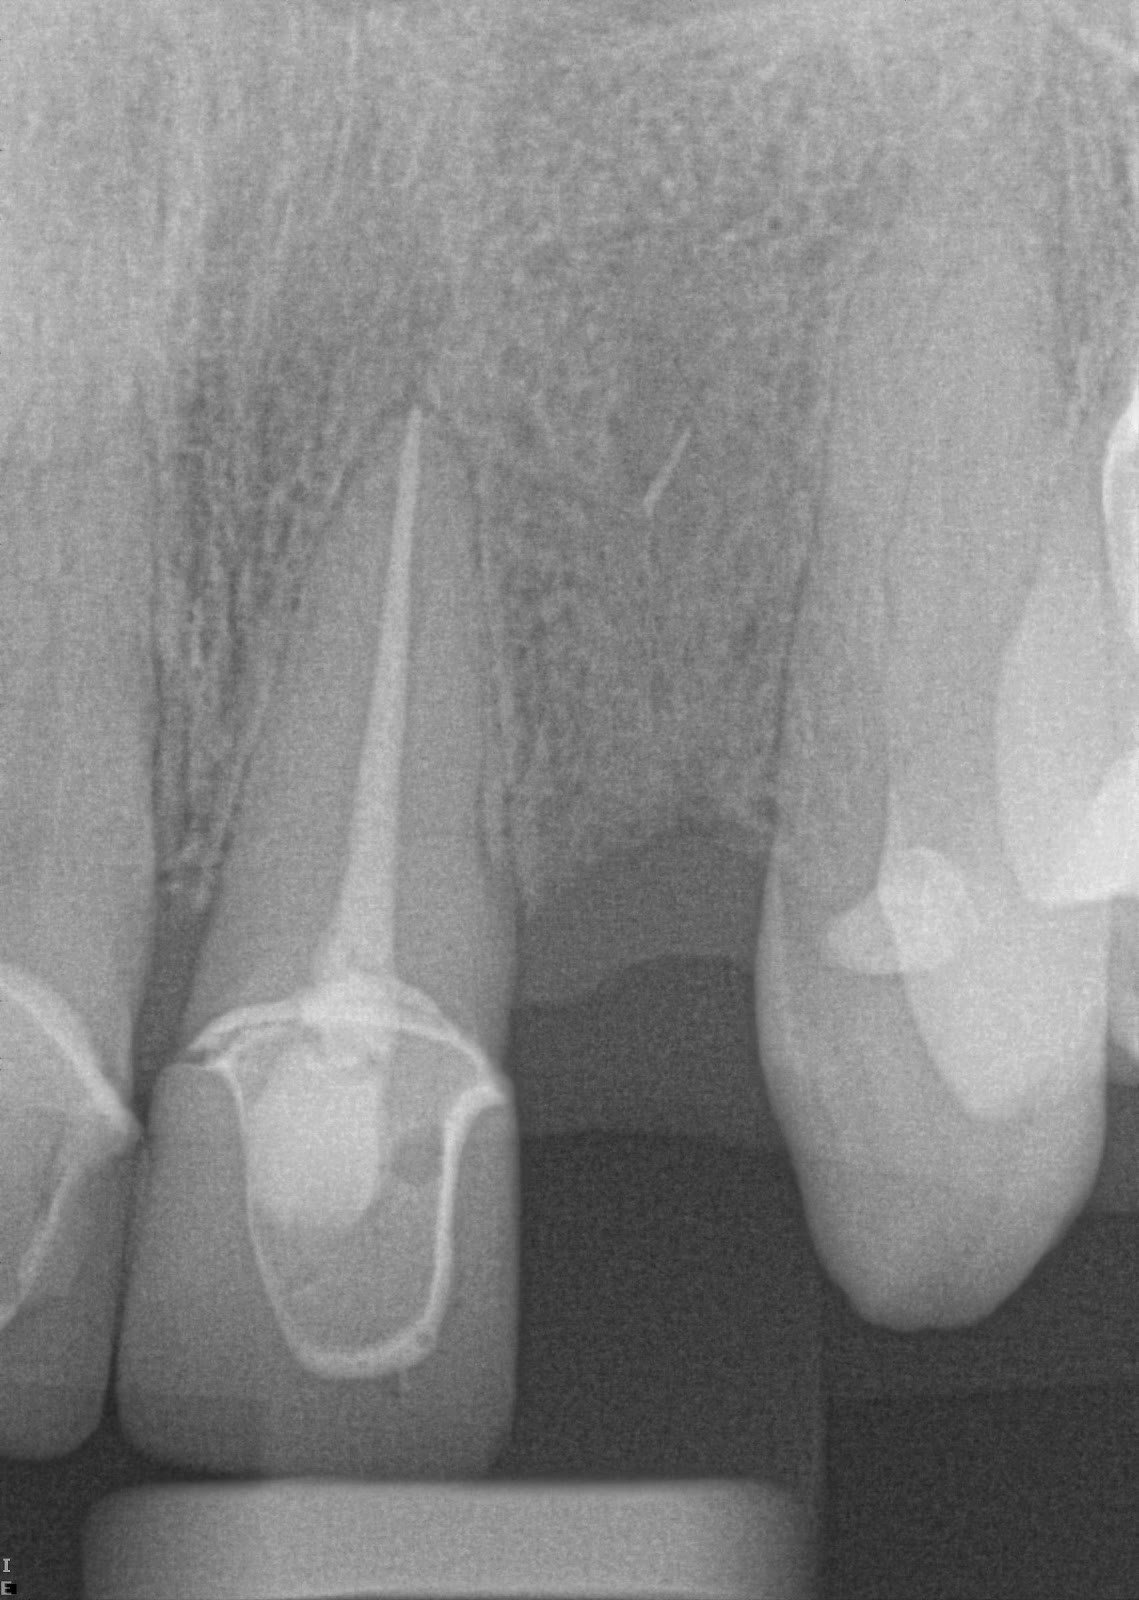

The patient presented is a 41 year old caucasian female that has been experiencing myofascial pain and has been dealing with an extracted tooth at site #10, as well as a missing tooth at site #20 for the past year and a half. Patient was referred to Dr. Richard Nejat for a holistic dental implant approach for tooth #10.

During the initial consultation, a general medical evaluation was performed by Dr. Richard Nejat to assess the patient’s medical history, teeth, gum, as well as jaw bone density and structure.

The consultation concluded that the patient appears to be in good health and it was decided that a Zirconia implant was to be inserted in order to replace tooth #10.